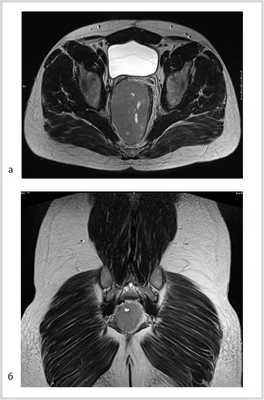

По данным магнитно-резонансной томографии (МРТ) от 10.02.2012, в полости малого таза пресакрально располагается опухоль размером 9,2×9×7 см. Верхний полюс ее на уровне тела S I позвонка, распространяется в параректальную клетчатку, тесно прилежит к прямой кишке, оттесняя ее влево (граница прослеживается). Нельзя исключить прорастание в кишку, стенки прямой кишки отечны. Опухоль прилежит к семенным пузырькам и предстательной железе (граница прослеживается); мочевой пузырь оттеснен кпереди и кверху; верхний полюс опухоли расположен между грушевидными мышцами, прилежит к передней поверхности крестца и копчика (граница прослеживается), нижний полюс опухоли расположен между волокнами мышцы, поднимающей задний проход; нижние ягодичные сосуды справа оттеснены кпереди, тесно прилежат к опухоли на протяжении 3 см (рис. 2).

Рис. 2. МР-томограммы малого таза. Пресакрально располагается опухоль размером 9,2×9×7 см. а — сагиттальный срез; б — фронтальный срез.

Учитывая данные иммуногистохимического исследования (G3, количество митозов >30%) и местный рецидив опухоли, больной консультирован химиотерапевтом из группы лечения сарком и радиологом, после чего решено провести неоадъювантную полихимиотерапию.

Проведено 6 курсов полихимиотерапии по схеме HD AI (препараты: ифосфамид 2000 мг/м 2 в/в в 1—5-й день, СД =20 000 мг; месна 2000 мг/м 2 в/в в 1—5-й день, СД =20 000 мг; доксорубицин 60 мг/м 2 в/в в 1-й день, СД =120 мг; нейпомакс по 300 мкг п/к в 6—15-й день).

Рис. 3. МР-томограммы малого таза. Опухоль уменьшилась в размере до 5,5×3,5×4 см, однако тесно прилежит к правой стенке прямой кишки. а — аксиальный срез; б — сагиттальный срез; в — фронтальный срез.